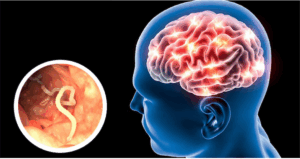

La situación más grave, añadió, sucede cuando sus huevos se transforman en larvas dentro del cuerpo, lo que se denomina cisticercosis. Estas se pueden alojar en músculos, ojos, piel, incluso en el cerebro.

“Si esto pasa hablamos ya de neurocisticercosis, que es una de las principales causas de epilepsia adquirida en México. Sus síntomas van desde dolores de cabeza crónicos hasta crisis epilépticas severas que afectan la calidad de vida”, detalló el integrante del Departamento de Medicina Molecular y Bioprocesos del IBt.

De acuerdo con la OMS, Taenia solium es causante de 30 por ciento de los casos de epilepsia en zonas endémicas donde hay cerdos en libertad cerca de donde viven las personas.